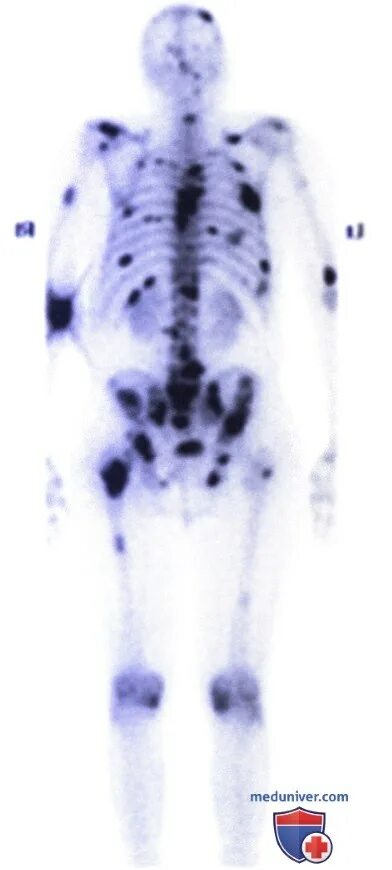

Метастазы в костях какая стадия